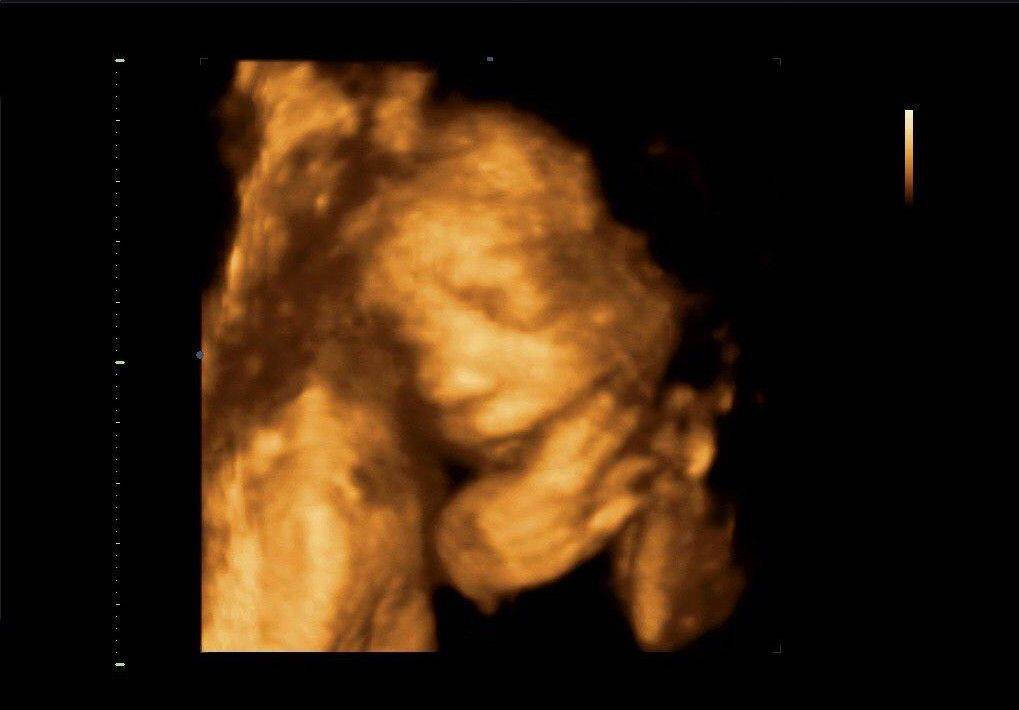

4D УЗИ позволяет получать то же самое объёмное изображение, но уже в режиме реального времени. Благодаря усовершенствованным технологиям картинку можно поворачивать под разными углами и наблюдать, как ребёнок двигается в матке, улыбается, шевелит ручками и ножками. В этом и заключается разница между 3D и 4D УЗИ. В первом случае картинка объёмная и яркая, но статичная. Во втором – реальное объёмное изображение плода. 4D рекомендуется делать с 20-й и по 33-ю неделю. Процедура занимает около 45 минут. Родители могут получить на руки видео на DVD-носителе.

Что касается 4D УЗИ, то оно представляет собой настоящий короткометражный «фильм» с единственным главным героем — малышом. Четырёхмерное ультразвуковое исследование показывает плод в движении в реальном времени. На записи можно увидеть, как он проводит своё время, чем занимается, понаблюдать за его мимикой, движениями и даже, если повезёт, порадоваться первой улыбке крохи. Ещё одним приятным и действительно нужным для будущих родителей бонусом является то, что эти бесценные и дорогие сердцу кадры можно записать на цифровые носители.